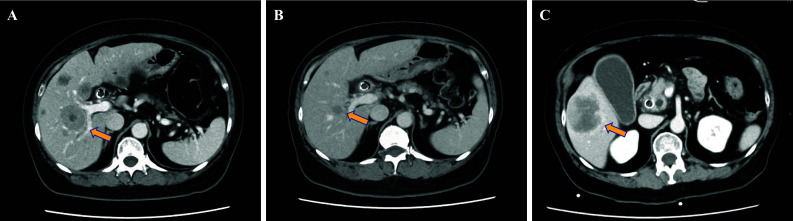

Patients with advanced duodenal carcinoma typically have a poor prognosis due to limited practical chemotherapy options. While studies on genotype-directed therapy in patients with duodenal carcinoma is progressing, clinical data assessing the efficacy of molecularly targeted therapy remains scarce. We report the case of a 65-year-old woman diagnosed with anaplastic lymphocyte kinase (ALK) fusion-positive advanced duodenal carcinoma. The patient had been treated with alectinib for approximately 2 years for ALK-positive duodenal carcinoma but developed progressive liver metastases, indicating alectinib failure. During the disease progression, circulating tumor DNA (ctDNA) sequencing revealed the emergence of ALK L1196M mutation, which demonstrated sensitivity to brigatinib. After switching to brigatinib, marked shrinkage of liver metastases was observed. The patient maintained brigatinib treatment for 7 months until tumor progression. This is the first report demonstrating the efficacy of brigatinib after alectinib failure in a patient with duodenal carcinoma harboring ALK fusion. Furthermore, this case suggests that ctDNA sequencing can detect specific acquired mutations and help expand optimal treatment options for patients.